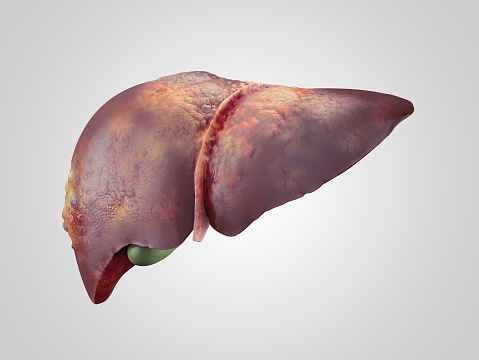

Everything we do and take in somehow affects our liver. Our liver performs over 500 functions that work to keep us healthy overall. But what do we do when the liver gets sick? Your best defense against a sick liver is to adhere to a healthy lifestyle as much as possible. It’s really that simple. ...click here to read more